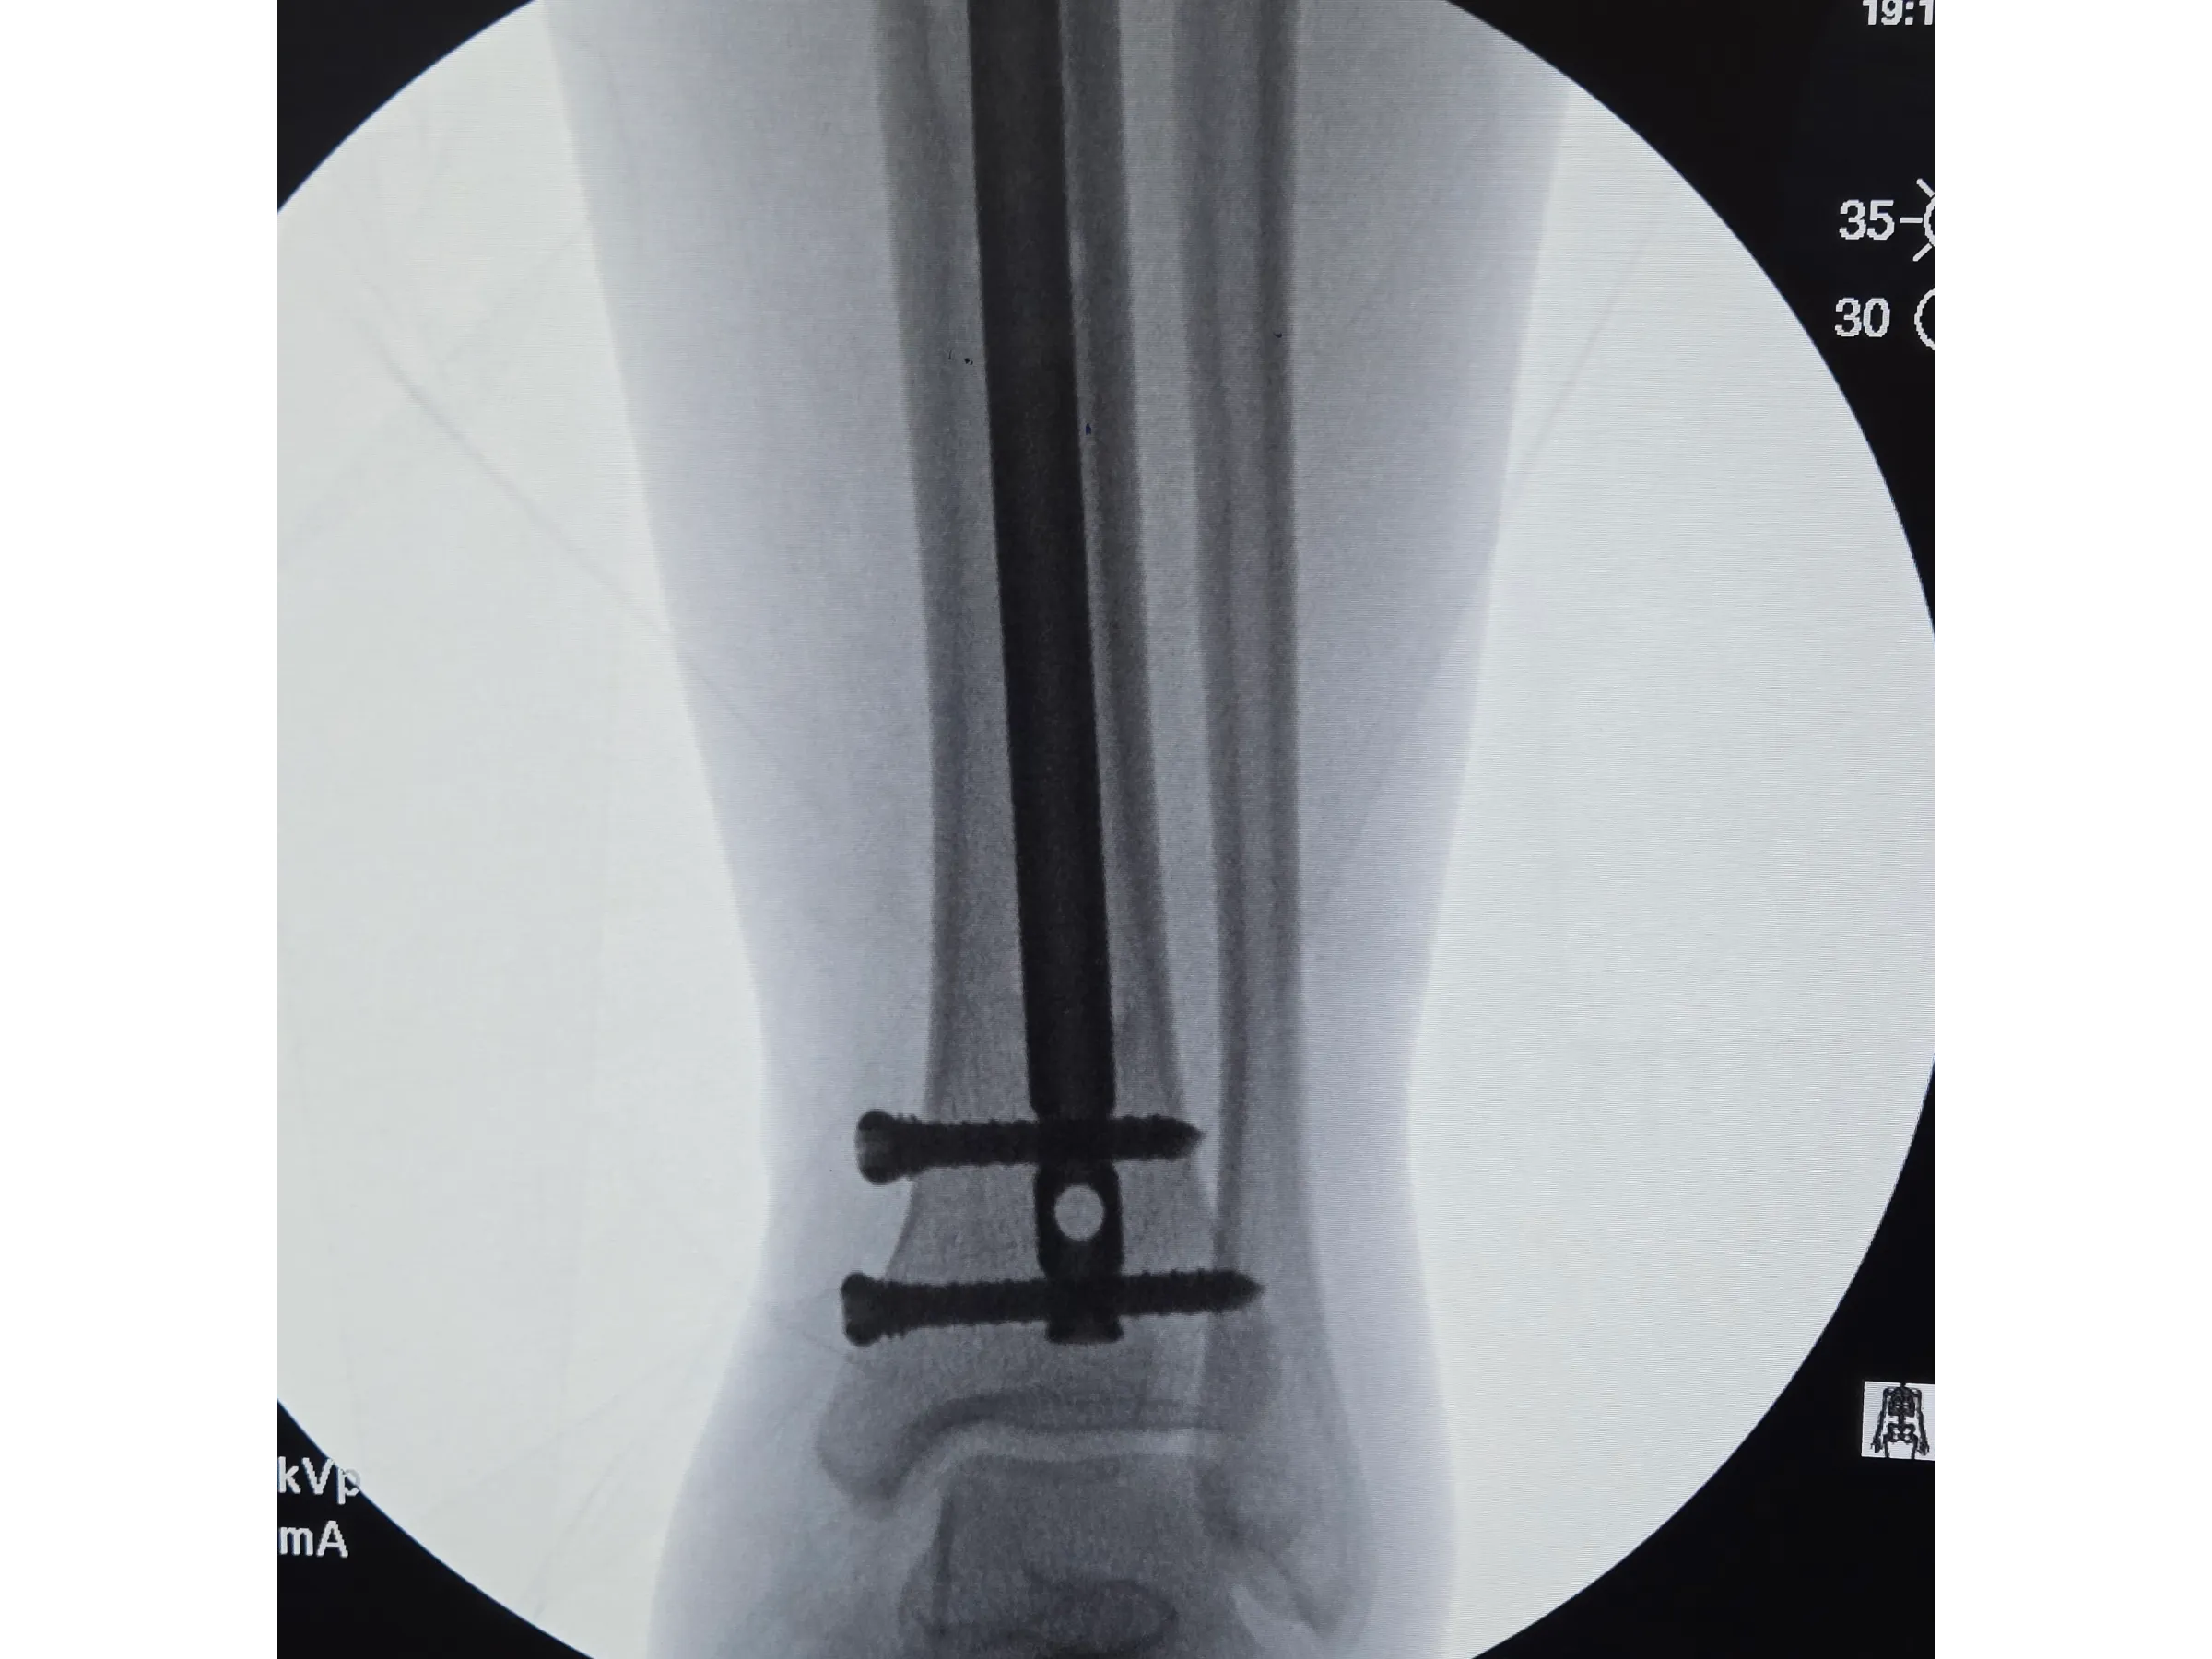

- Bloqueios proximais e distais com abordagem minimamente invasiva;

- Bloqueios Proximais e Distais Minimamente Invasivos: Execução de bloqueios cruzados e distais com pequenos portais e controle por intensificador;